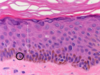

What is shown by letters a-e in this picture?

a - stratum basale

b - stratum spinosum

c - stratum granulosum

d - stratum lucidum

e - stratum corneum

What is shown by the letters in the high magnification of keratinised squamous epithelium?

b - stratum spinosum

c - stratum granulosum

e - stratum corneum

What is shown in this image?

resin section of stratified squamous epithelium